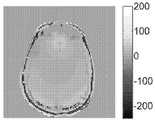

도 14는 에코 분할 방법 및 스핀 에코 방법을 이용하여 MRF로부터 획득된 T1 및 T2 값들을 비교한다.Figure 1 shows a number of echo paths associated with a split echo sequence.

14 compares T1 and T2 values obtained from the MRF using the echo splitting method and the spin echo method.

도 14는 QUEST MRF 및 스핀 에코 방법들로부터 획득된 T1(좌측)과 T2(우측) 값들을 비교한다. 도 14는, QUEST MRF를 사용하여 포착된 T1 및 T2 값들이 종래의 방법을 사용하여 포착된 T1 및 T2 값들과 매우 양호하게 일치한다는 것을 도시한다.Figure 14 compares T1 (left) and T2 (right) values obtained from QUEST MRF and spin echo methods. Figure 14 shows that the T1 and T2 values captured using the QUEST MRF coincide very well with the T1 and T2 values captured using conventional methods.